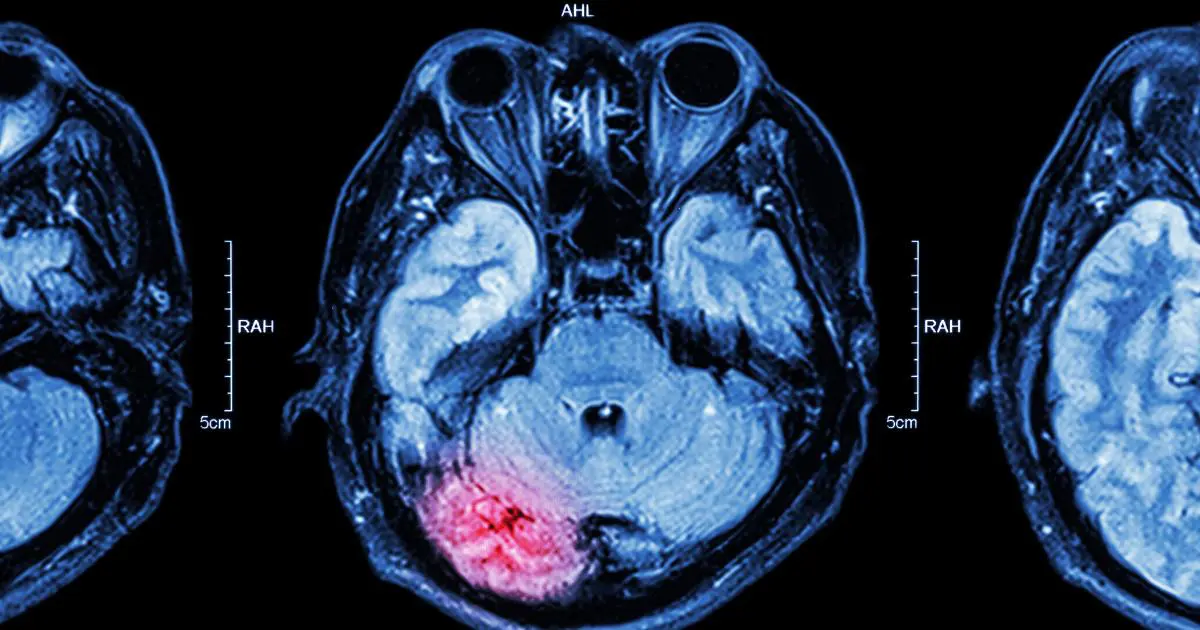

What’s the Difference Between an Anoxic vs. Hypoxic Brain Injury?

An anoxic brain injury occurs when there is no supply of oxygen to the brain at all. When the brain has been deprived of oxygen for more than four minutes, the brain cells die, and the injured person may be declared braindead. It is uncommon for someone to recover from a severe anoxic brain injury.

Hypoxic brain injuries are severe, but they often occur when the brain is deprived of some oxygen. While the brain may still have access to some oxygen, the amount of oxygen provided to the brain could be severely limited, ultimately causing symptoms to develop. Someone with a hypoxic injury could end up in a coma for days, weeks, or months. Symptoms of a hypoxic brain injury include: